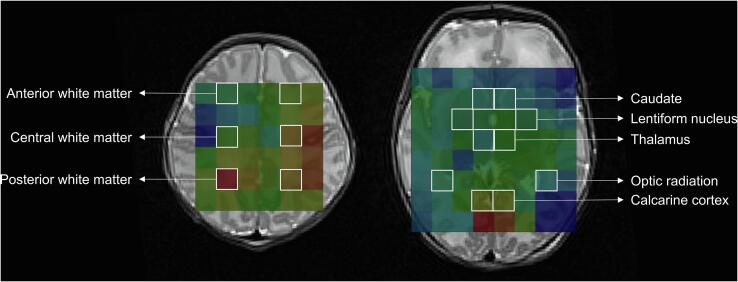

MRS PRESS data were analysed using TARQUIN (Totally Automatic Robust Quantification In NMR) version 4.3.10 in order to suppress the water signal (Carlin et al., 2019, Wilson et al., 2011). The spectra were referenced to a combination of total choline‐creatine‐NAA‐lipids. Due to significant spectral overlap, total N-acetylaspartate (NAA) included a combination of N-acetylaspartate and N-acetylaspartylglutamate, and total choline (Cho) included a combination of glycerophosphocholine and phosphocholine. Lactate was also measured. ROIs were placed at in the anterior, central, and posterior white matter, caudate, lentiform nuclei, thalamus, optic radiations, and calcarine cortex (Fig. 3) (Chau et al., 2009). Values from left and right hemisphere were averaged for analysis.

Fig. 3.

Regions of interest for MR spectroscopic imaging (MRSI). MRSI superimposed on axial T2-images at the level of the centrum semiovale (left image) and basal ganglia (right image), showing the eight bilateral regions of interest.